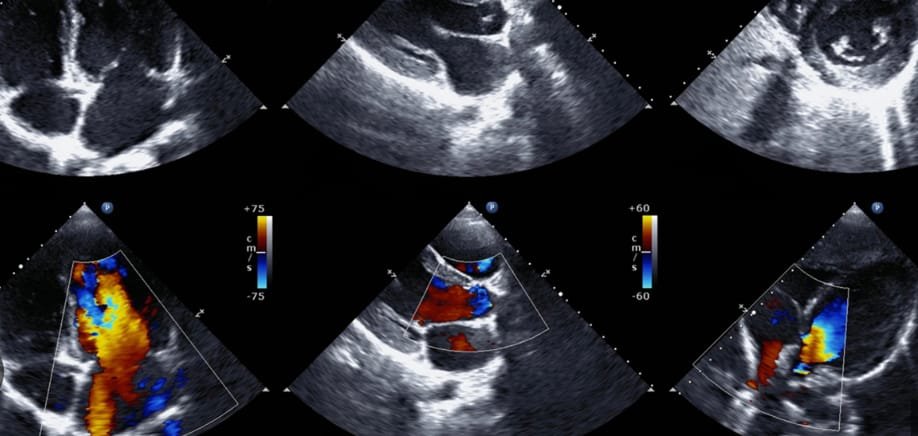

- an echocardiogram to exclude structural heart disease that is sometimes impossible to detect with an examination. This can be called a sonar of your heart.